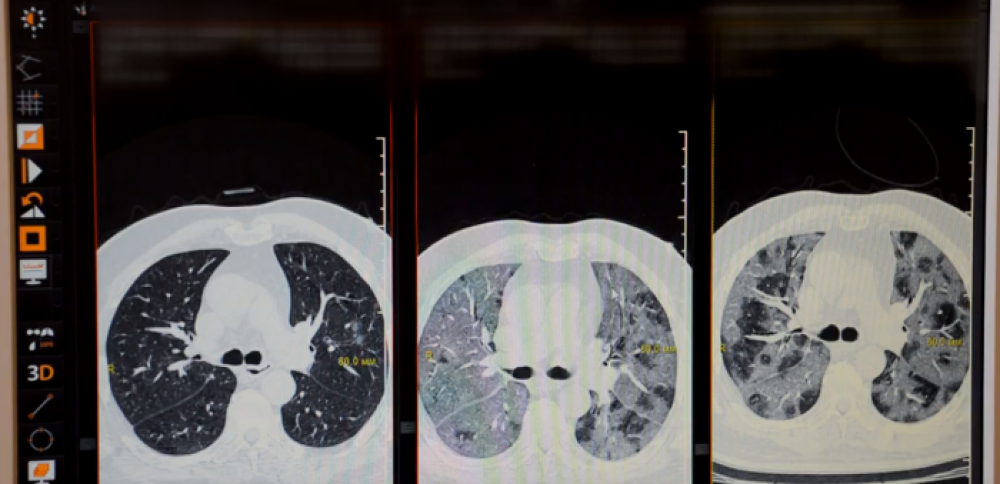

ԱվելինԵ՞րբ պետք է դիմել բժշկի և ի՞նչ զարգացում կարող է ունենալ ատիպիկ թոքաբորբը

ՀՀ առողջապահության նախարարությունը տեսանոյւթ է հրապարակել այն ամսին, թե ե՞րբ պետք է դիմել բժշկի և ի՞նչ զարգացում կարող է ունենալ ատիպիկ թոքաբորբը: «Որո՞նք են կորոնավիրուսային հիվանդությամբ պայմանավ ...